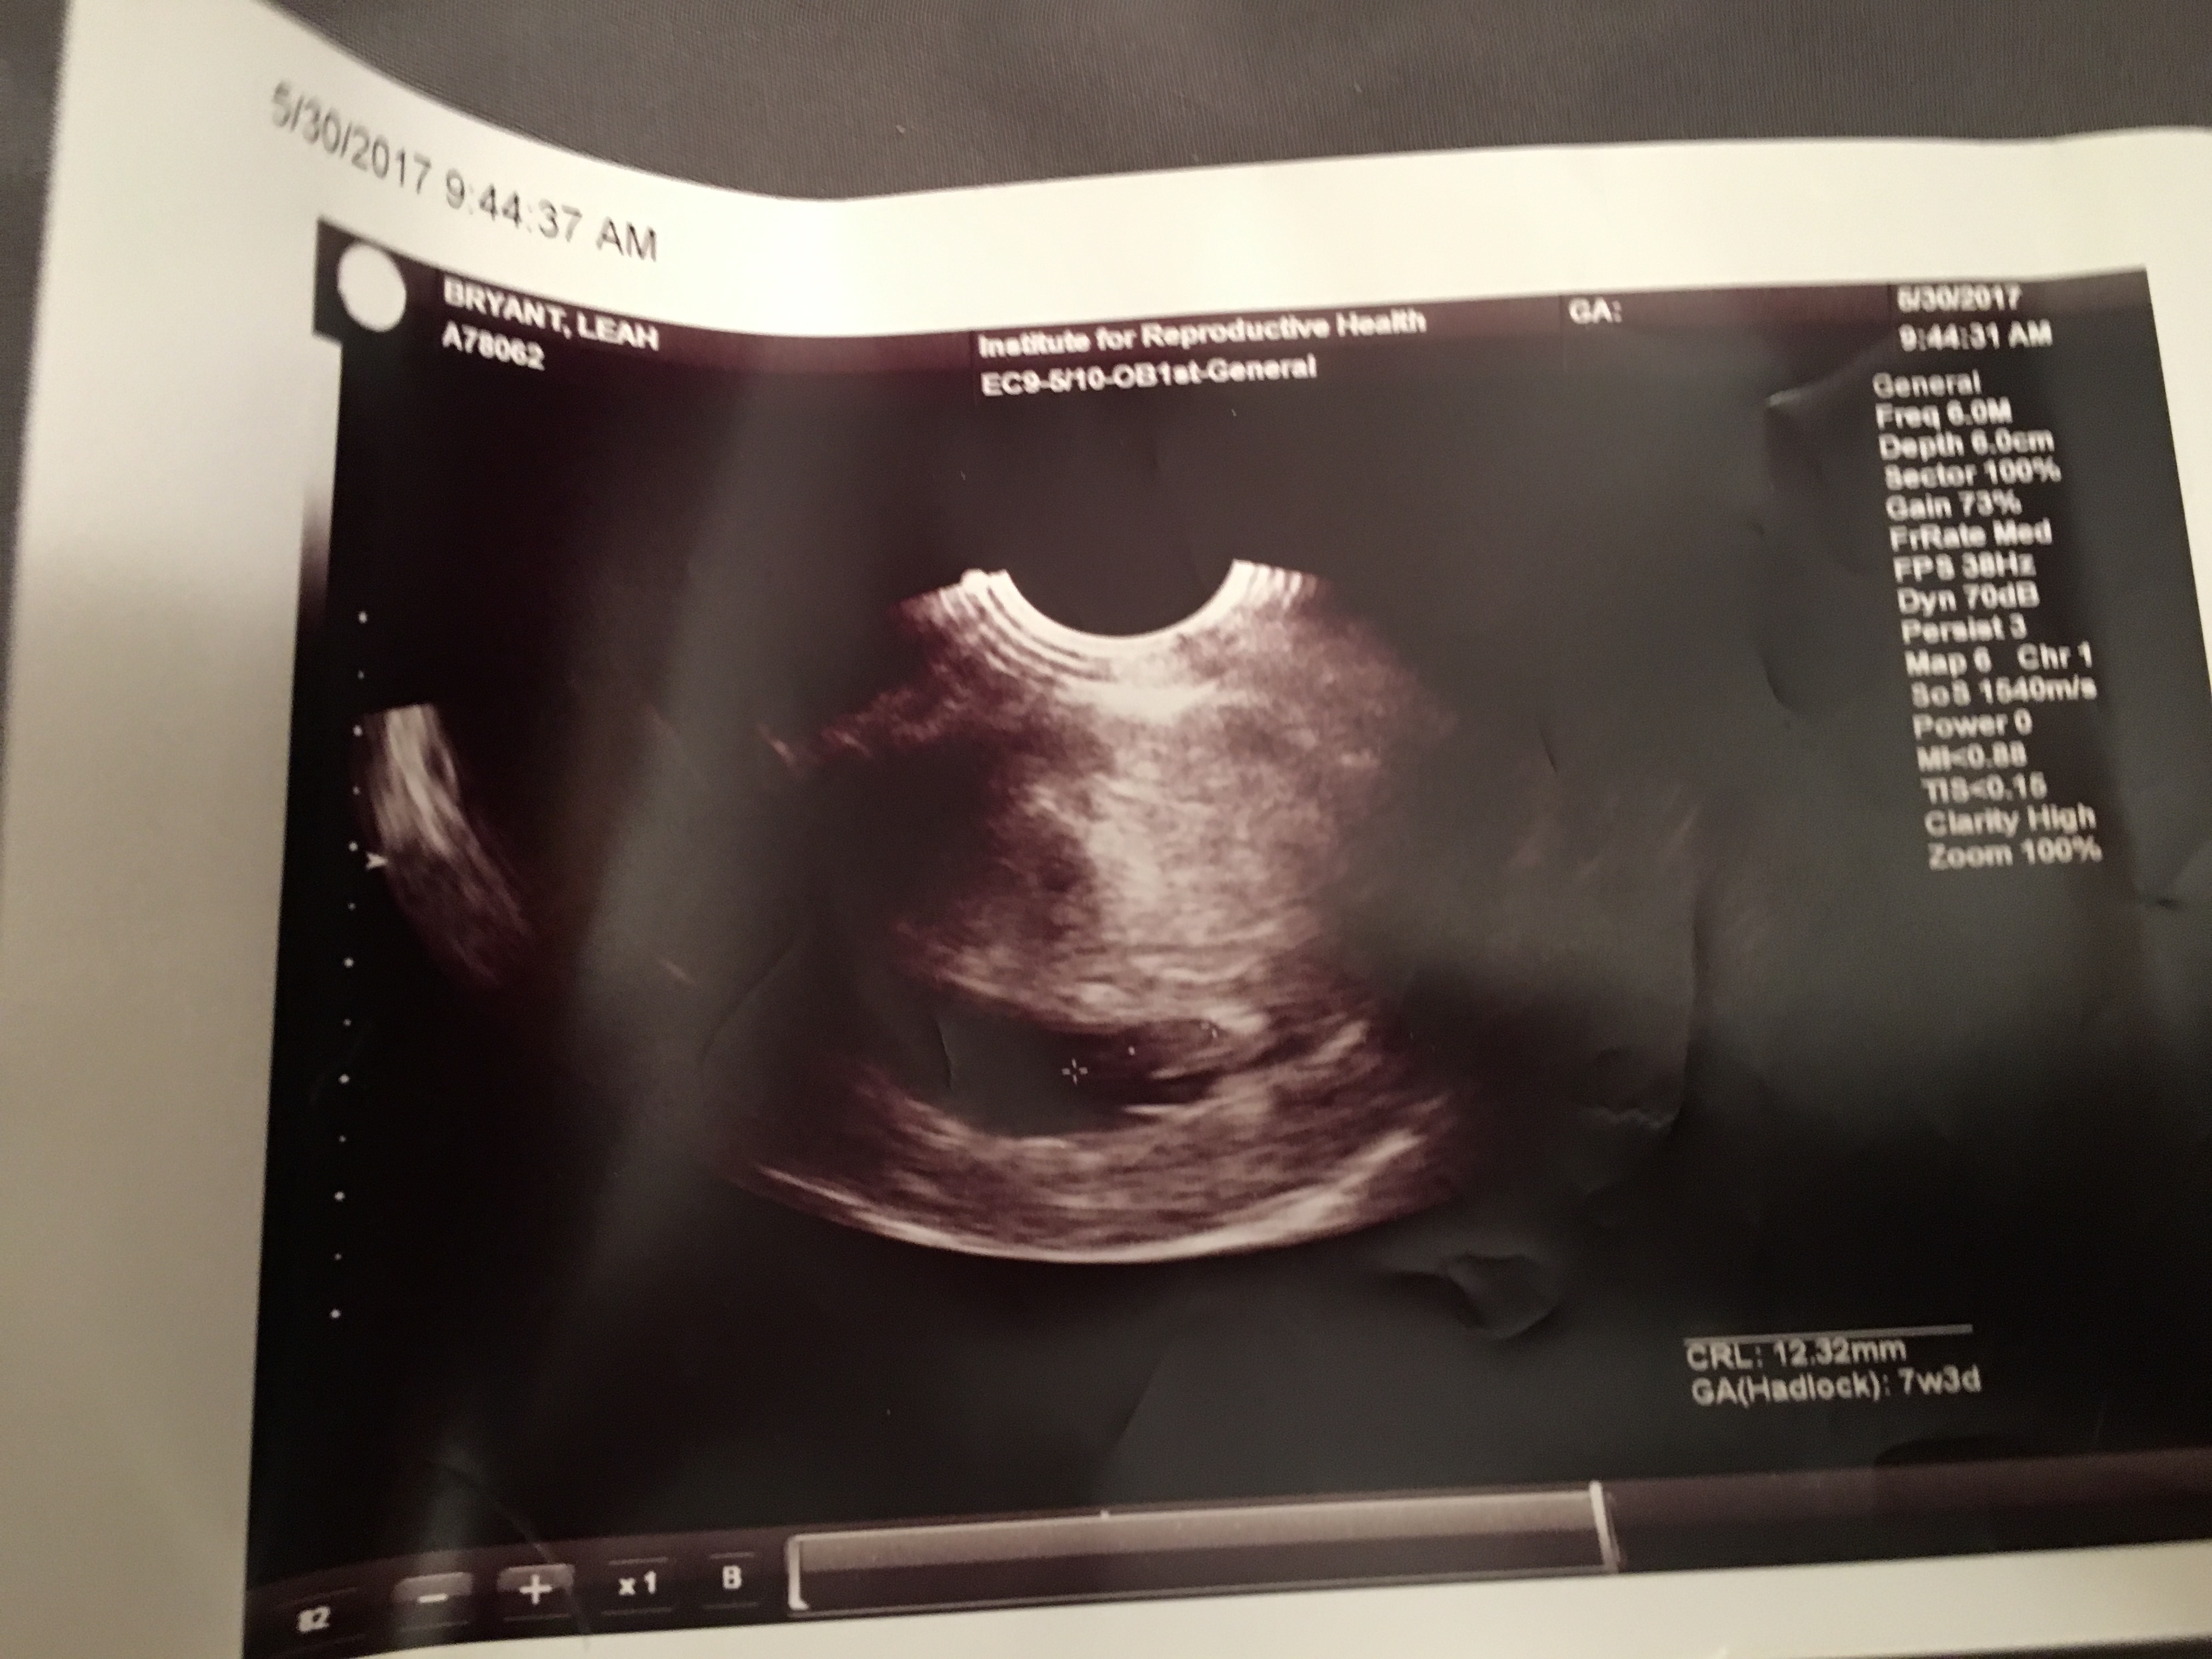

At first, neither one of us had an idea of what we were looking at. That’s when he put the mouse at one end and then the other end of our little one. Yes, just one – we are completely stoked about that! With the infertility drugs and me being over 35, there was a possibility of twins. Which would have been completely fine too!

Then from a different angle he was showing us, we could see the heart beating away! That’s when for whatever reason, I decided to reach out and touch the screen. Probably that goober side taking over again. haha

The doctor said that all looked as should and to come back in two weeks. He then picked up his little spin wheel to tell us our due date. (I had already googled this and knew it was around January 13/14th, but it’s always nice to have the official due date from the doctor!)

Our due date is January 13th, 2018! Mark your calendars for our little miracle to arrive! WOOHOO